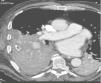

We briefly review the literature of BAA based on radiological findings of an exceptional case of an 74 years‐old male, with no previous trauma or lung disease, that was admitted to our emergency department with hemoptysis and was found to have ruptured BAA in computed tomography (CT). The chest angio‐CT (CT performed with intravenous contrast) revealed a 2.4cm BAA (Fig. 1) contiguous with a large right bronchial artery, that is originated from the dilated right intercostobronchial trunk, associated intrapulmonary hematoma of the lower right lobe (secondary to sustained ruptured intrapulmonary BAA) and homolateral hemothorax.

No apparent lung parenchymal or bronchial disease (namely bronchiectasis) was seen.